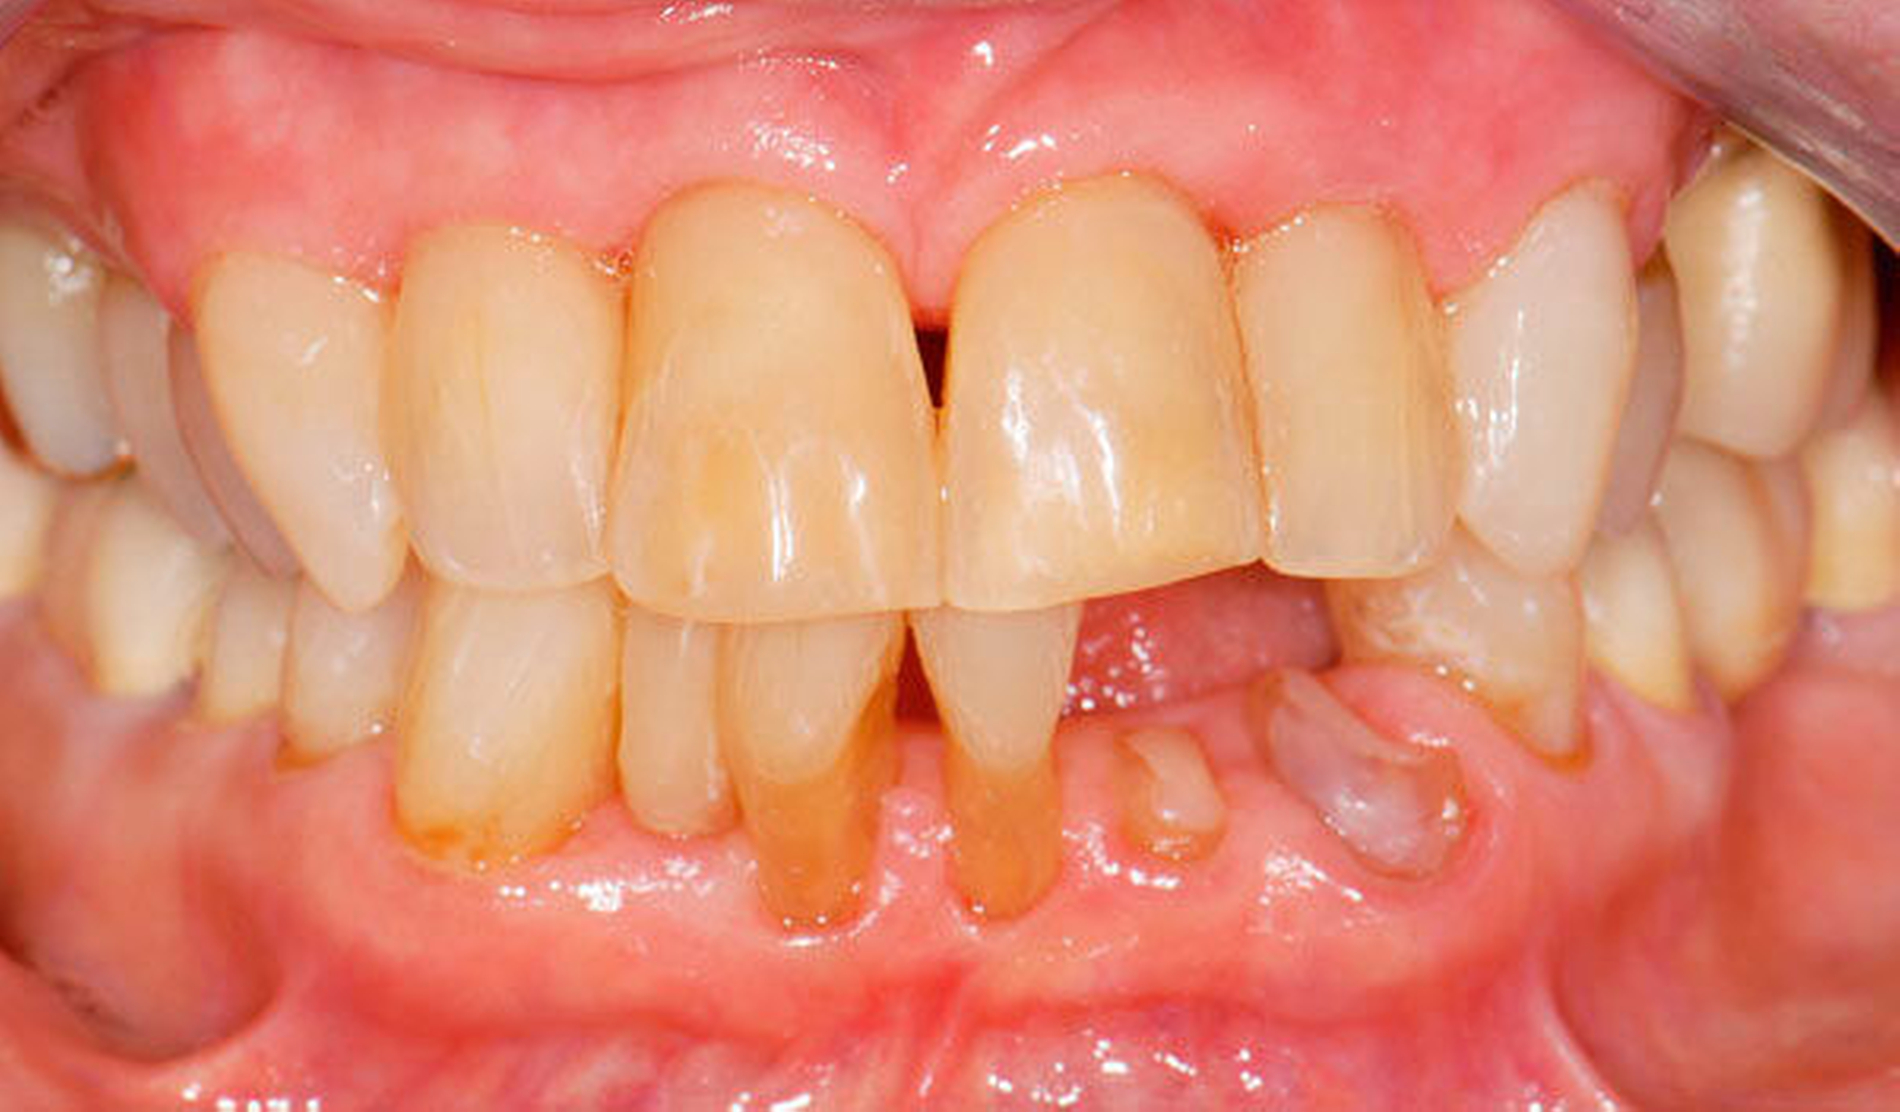

2. Management von Abrasionen, Attritionen und Erosionen

Fast alle bezahnten Senioren weisen deutliche Zeichen von altersentsprechenden Abrasionen, Attritionen und Erosionen auf. Bei langsamer Progression ist in restaurativer Hinsicht meist ein Zuwarten beziehungsweise eine individuelle Prävention indiziert. Bei schneller Progression empfiehlt sich hingegen eine rechtzeitige, teilweise von den Präparationsgrenzen unabhängige „Verschalung“ betroffener Areale mit direkt eingebrachtem Komposit unter Berücksichtigung der Antagonistensituation. Zuweilen müssen unter Abwägung der Vor- und Nachteile scharfe antagonistische Höckerspitzen vorsichtig subtraktiv abgerundet werden, wobei allerdings die Gefahr einer Dentinfreilegung besteht (Abbildung 2, Tabelle 2).